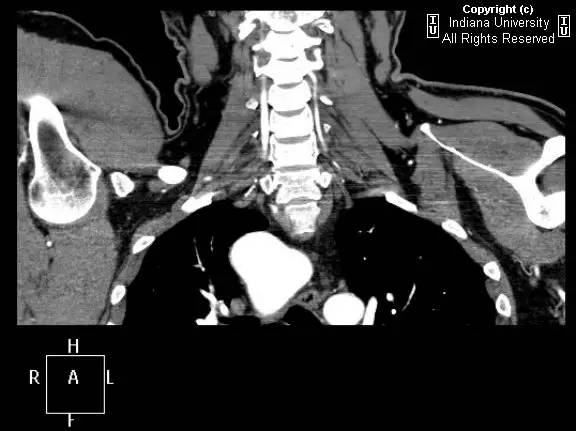

【影像学表现】胸部平片示右位主动脉弓,肺动脉突出,双肺清晰。CT示右位主动脉弓,并右位降主动脉,迷走左锁骨下动脉起自后方,从食管后走形形成血管环。迷走左锁骨下动脉与憩室相关(Kommerell)。食管因左锁骨下动脉及憩室而向前移位。

【诊断】右位主动脉弓并血管环形成、迷走左锁骨下动脉并Kommerell憩室

Right-sided aorticarch, with vascular ring and aberrant left subclavian with Kommerell\’sdiverticulum